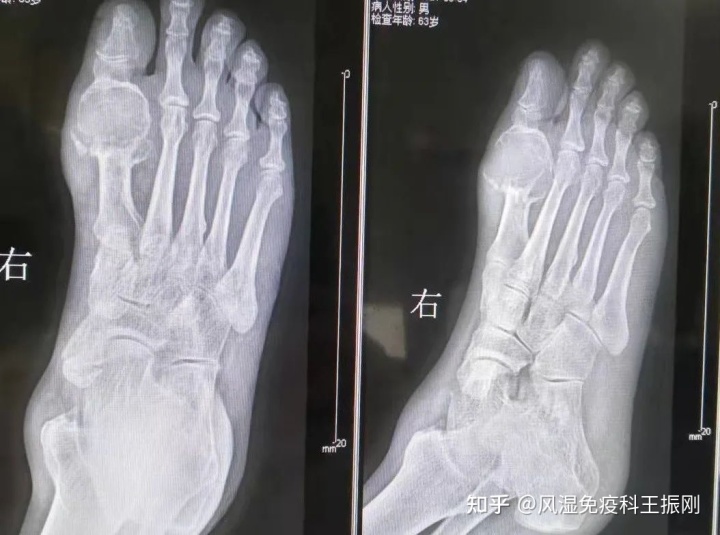

在我的安排下,李先生做了血常规、尿常规和DR检查。DR片送到我手上时,我吓了一跳:影像学显示,李先生的右脚第一跖趾关节骨质已经完全被尿酸盐结晶腐蚀,而右脚踝关节的骨质也破坏殆尽。

DR片下李先生右脚大脚趾和踝关节尿酸盐结晶沉积情况